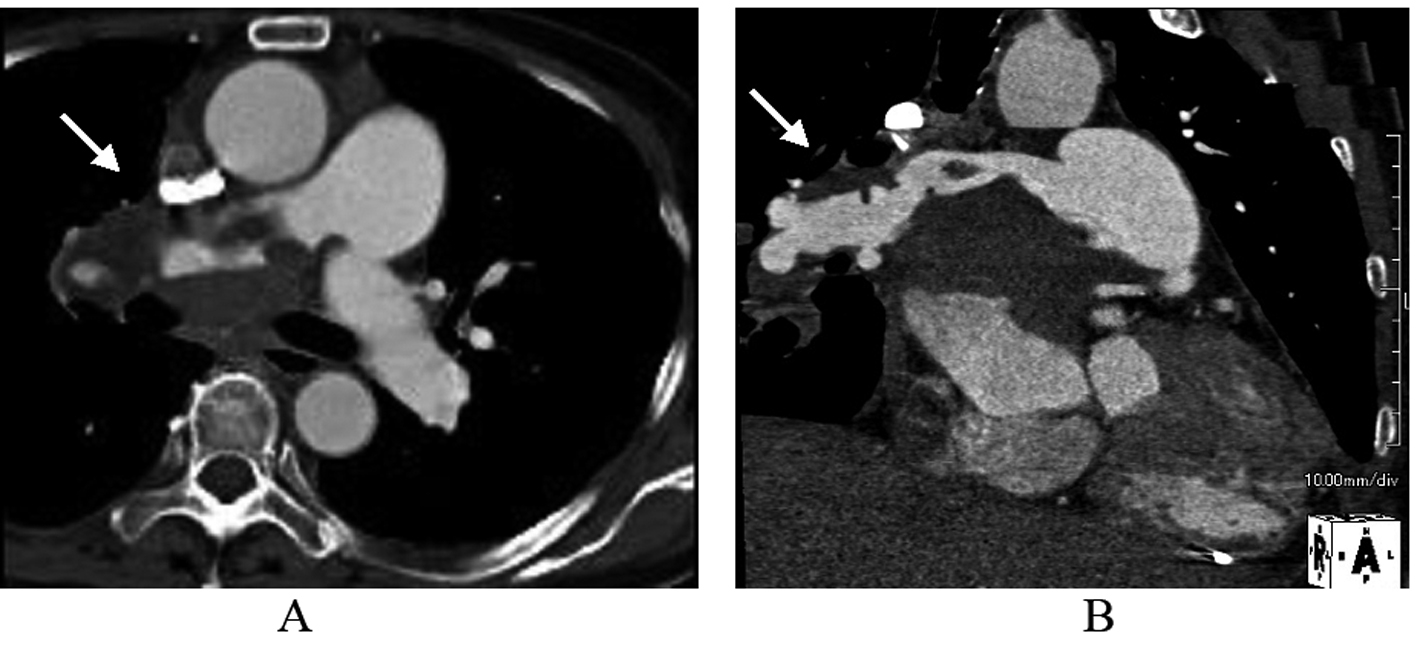

TTE revealed dilatation of the main pulmonary trunk and high systolic pressure gradient across the tricuspid valve of 49 mmHg that is consistent with pulmonary hypertension. There was a thrombus-like mass in the right pulmonary artery and around the left atrium. CT scan similarly revealed a large mass in the proximal portion of right pulmonary artery and around the left atrium, but no abnormal mass detected in the lung and other organs (Fig. 1). However, lung scintigraphy demonstrated little visualization of the right lung on technetium-99m macroaggregated albumin (99mTc-MAA) perfusion scan. Ventilation scan with krypton-81m (81mKr) gas was normal (ventilation-perfusion mismatch). Cardiac catheterization demonstrated mean pulmonary artery pressure of 40 mmHg that indicated pulmonary hypertension. Right pulmonary angiography demonstrated vascularized mass with a fistula from the right pulmonary artery to the left atrium (Fig. 2). To confirm this suspected malignant features and the extent of disease, 18-fluorodeoxyglucose positron emission tomography (FDG-PET) was performed. FDG-PET revealed a large mass at the area of the right pulmonary artery and the bilateral atira with intense uptake of FDG. The maximum standard uptake value (SUVmax) was 25.2. No other undue hypermetabolic lesions were noted elsewhere (Fig. 3).

![]() Click for large image | Figure 1. The image of Contrast-enhanced computed tomography scan. Early arterial phase showed massive filling defects in the proximal portion of right pulmonary artery and around the left atrium in axial (A) and sagittal (B) views. |